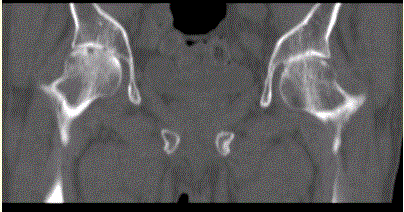

问题 患者女,53岁,双髋关节痛。双髋关节CT平扫冠状重组影像如下图。 可能的诊断为

选项 A.右侧股骨头缺血性坏死,左髋关节退行性变 B.双髋关节退行性变 C.双髋关节类风湿性关节炎 D.强直性脊柱炎累及双髋关节 E.右髋关节退行性变,左髋关节未见异常 F.双髋关节结核性关节炎 G.双髋关节滑膜炎

答案 CD